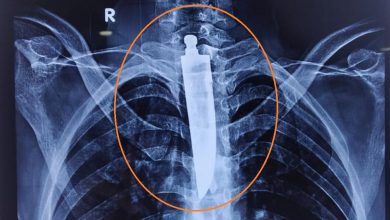

इस युवक को लोहा खाना पड़ा भारी, फेफड़े में जा फंसा 6 इंच का…